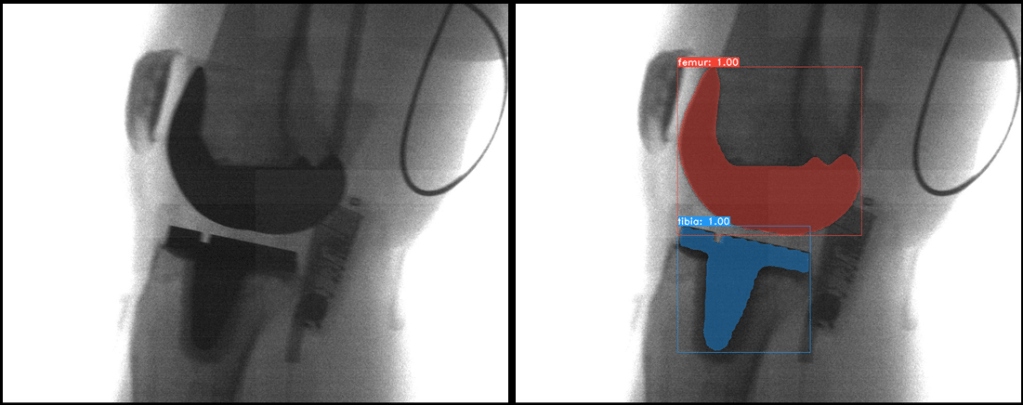

Machine Learning

Leveraging machine learning techniques for image segmentation and image registration in implanted knees holds significant promise. By training algorithms on large datasets of medical images, machine learning can effectively identify and separate different anatomical structures in images, enabling precise segmentation of bone, implant components, and surrounding tissues. Moreover, machine learning-driven image registration can align pre- and post-operative images, allowing for accurate comparisons and assessments of implant placement, alignment, and changes over time. This innovative approach enhances clinicians’ ability to monitor the condition of implanted knees, optimize surgical procedures, and ultimately contribute to improved patient care and outcomes.